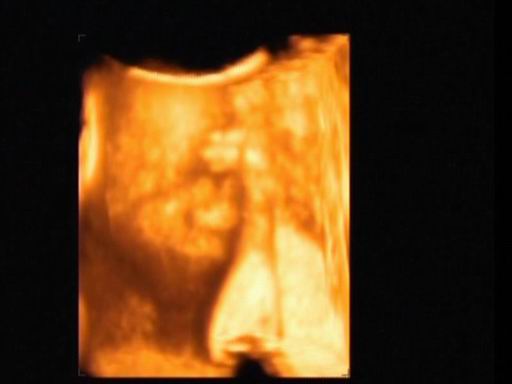

Mégsem múlt héten voltam dokinál, mert elmaradt a rendelés örültem....Így tegnap voltam dokinál minden rendben, meg du. 4D-n voltunk. Tényleg fiú és jó nagy a korához képest,több, mint egy héttel nagyobb 860 gr. :D Majd próbálok kivenni a videóból képet.